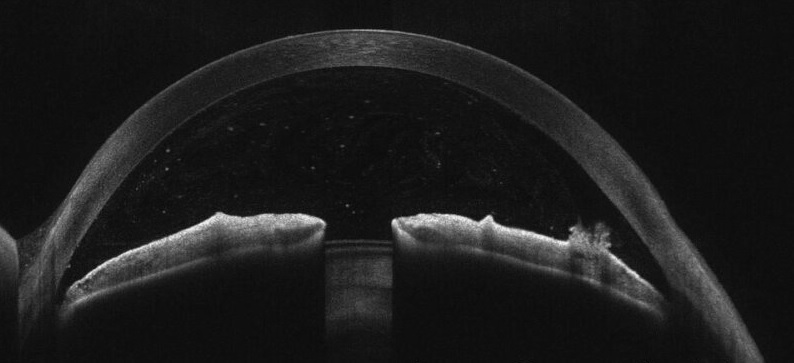

Передній відрізок після іридотомії